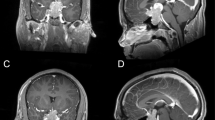

Among patients in the Severance Hospital Pituitary Tumor Cohort, 232 subjects received transsphenoidal adenomectomy following a diagnosis of GH-secreting pituitary adenoma from January 2012 to January 2017 at Severance Hospital, Yonsei University College of Medicine, Seoul, Korea. All the enrolled patients were single ethnicity, Korean. GH-secreting pituitary tumors were confirmed by measuring serum insulin-like growth factor-1 (IGF-1) and nadir GH levels during the 75-g oral glucose tolerance test. Immunohistochemical staining of the operated pituitary tumors was performed for GH, prolactin, luteinizing hormone, follicle-stimulating hormone, thyroid stimulating hormone, and adrenocorticotropic hormone. Pituitary tumors expressing hormones other than GH were excluded from this study. Finally, the tumor tissues of 140 patients with acromegaly expressing only GH were evaluated. No patients had a family history of pituitary adenoma. Pituitary tumors were classified based on dynamic magnetic resonance imaging of the sella turcica and parasellar region according to the modified Hardy radiological classifications, as described previously35.